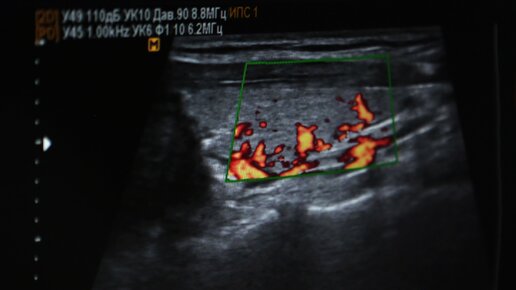

Что означает желтое тело на УЗИ?

Иногда женщина в кабинете УЗИ может услышать, что у нее обнаружено желтое тело в яичнике по результатам исследования. Но что это такое? Когда выполняют УЗИ женщине по поводу проверки яичников, она может услышать такую фразу: у вас желтое тело в яичнике. Что это значит, не всем известно и понятно. О том, что это за явление и не опасно ли оно, aif.ru рассказала к. м. н., врач-акушер-гинеколог акушерского физиологического отделения МОНИИАГ Яна Андросова. Обычно желтое тело могут найти при проведении УЗИ малого таза в яичнике...